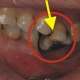

Mit den Zähnen ist es so ähnlich wie mit den Gliedern in einer Kette. Jeder Zahn ist von seiner Architektur her perfekt auf seine jeweilige Aufgabe aufgebaut. Doch das System funktioniert nur so gut wie das sprichwörtlich schwächste Glied in der Kette. Der Verlust nur eines einzelnen Zahnes bedingt, dass eine unterbrochene Zahnreihe entsteht und das Zusammenarbeiten der Zähne gestört ist. In aller Regel entsteht ein so genanntes instabiles System. Das bedeutet, dass der Zahnverlust zwangsläufig zu negativen Veränderungen führt.

Zahnlücken sind nicht nur äshtetisch negativ

...sondern haben zahlreiche ungünstige Auswirkungen.